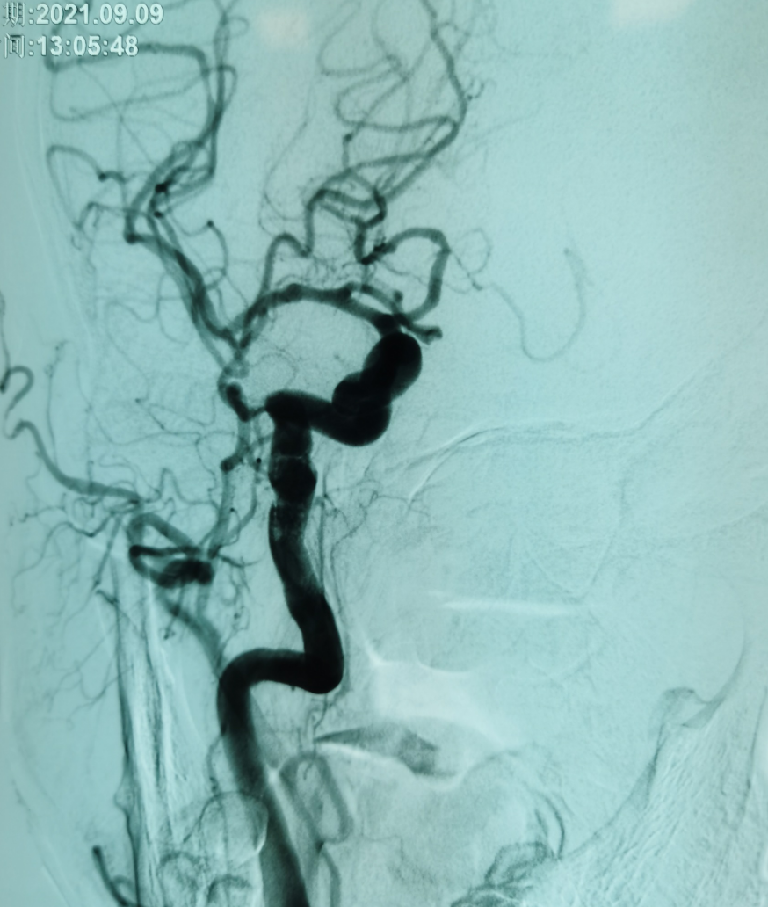

患者盛某某,因反复发作性头晕多次入院,完善CTA示左侧椎动脉狭窄,应用多种药物效果欠佳,魏华明主治医师考虑为椎动脉狭窄所致后循环缺血,给予椎动脉支架植入血管成形术,术后头晕症状完全消失。

左侧椎动脉狭窄